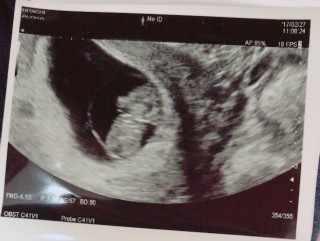

通勤電車で立っていたら立ちくらみがし途中駅の休憩室で休ませてもらいました。以前同じ症状で失神したこともあり主人に迎えに来て貰いそのまま産婦人科へ受診。脳貧血だそうです。血液は赤ちゃんへ優先的に送られるから今後も早めに座るなど気をつける様にとのこと。赤ちゃんは、順調に育っていました!手足がはっきり見れて嬉しかった!

逆さで左を向いてます。足をピーンとハの字に開いたドラえもんがいました。 大きさはもう9w0dありました。 フライドポテト食べすぎかしら…